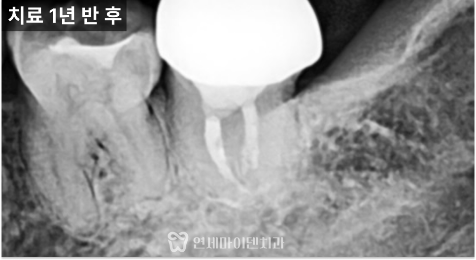

하지만 통증뿐 아니라

뼈까지 생겨야 치료의

성공이라 할 수 있습니다.

J자 형태로 보이던

뼈 소실 부위가 채워진

모습을 확인할 수 있었습니다.

뿌리 끝 염증이 치아 종축을

따라 J 자 형으로 녹아 있을 경우

크랙을 의심하게 됩니다.